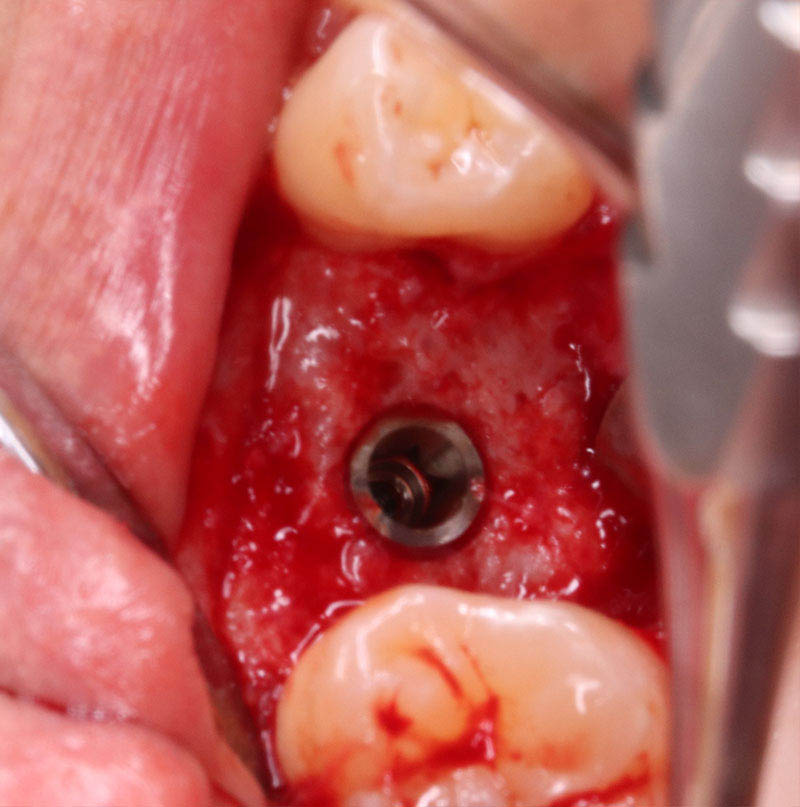

インプラント埋入手術

インプラントの埋入に関しては1回法で行いました。抜歯した部位の骨はしっかりと治癒していました。インプラント埋入後はヒーリングキャップを装着しました。手術時は特に大きな問題はなく無事に手術が終了しました。インプラントの露出を避けるためにも骨幅が少しでも広いところに埋入するために理想的な位置よりは少し後ろになっています。